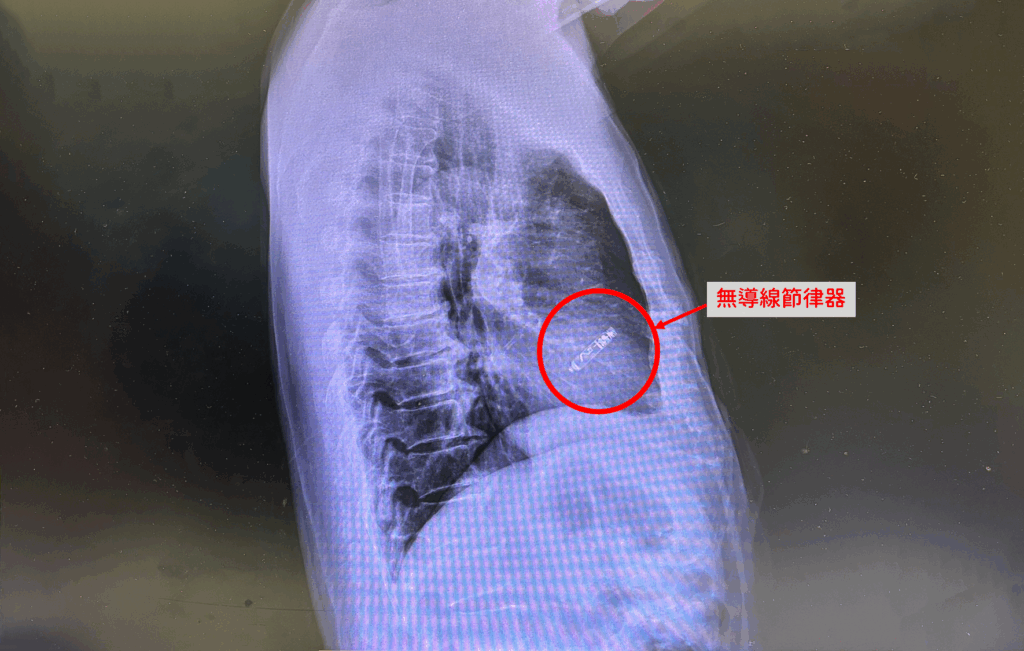

林圀宏表示,無導線節律器最大的優點,就是沒有導線,也沒有胸前傷口。醫師經由鼠蹊部股靜脈,以導管將圓柱狀節律器送入心臟,並以其前端螺旋構造固定於心房或心室內,節律器直接釋放電流刺激心房或心室的肌肉收縮,改善心跳緩慢問題,由於裝置與穿刺傷口距離遠,即使局部傷口出現感染,也不需移除心臟內的節律器,大幅降低併發症風險。

心臟科醫師林圀宏表示,過去10年,無導線節律器多僅能置放於右心室,去年底起,新一代裝置已可置放於右心房,為竇房節功能障礙患者提供更合適選擇。若病人僅有竇房節問題,可單獨置放心房節律器;若同時合併房室傳導阻斷,則需分別於心房與心室各置放一顆,兩者雖無導線連接,但可透過藍牙技術彼此溝通,維持心房先收縮、心室後收縮的生理節律。